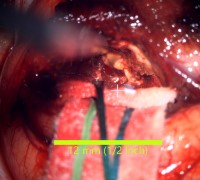

Intraoperative video showing final removal of the lesion.